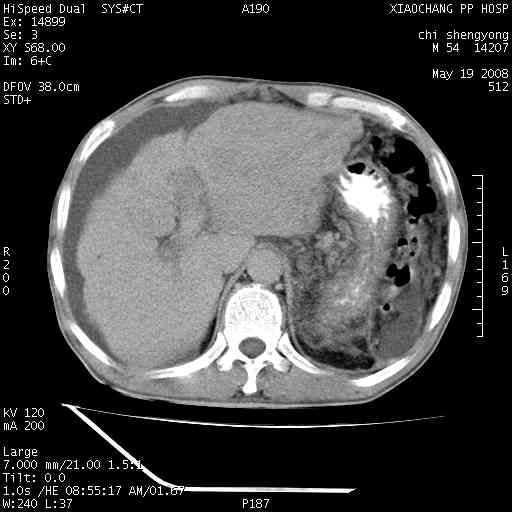

以下是引用zjzjr在2008-5-21 10:52:00的发言:[br]肝左叶巨块型肝癌伴门静脉左支瘤栓形成.肝硬化、腹水,胃底静脉曲张,脾术后改变。

以下是引用随光逐影在2008-5-21 16:20:00的发言:[br]1)肝左叶肝癌伴门静脉左支瘤栓形成,腹膜后淋巴结转移。2)肝硬化、腹水、胃底静脉曲张。3)胆囊炎。4)脾脏缺如,为切除术后所致。